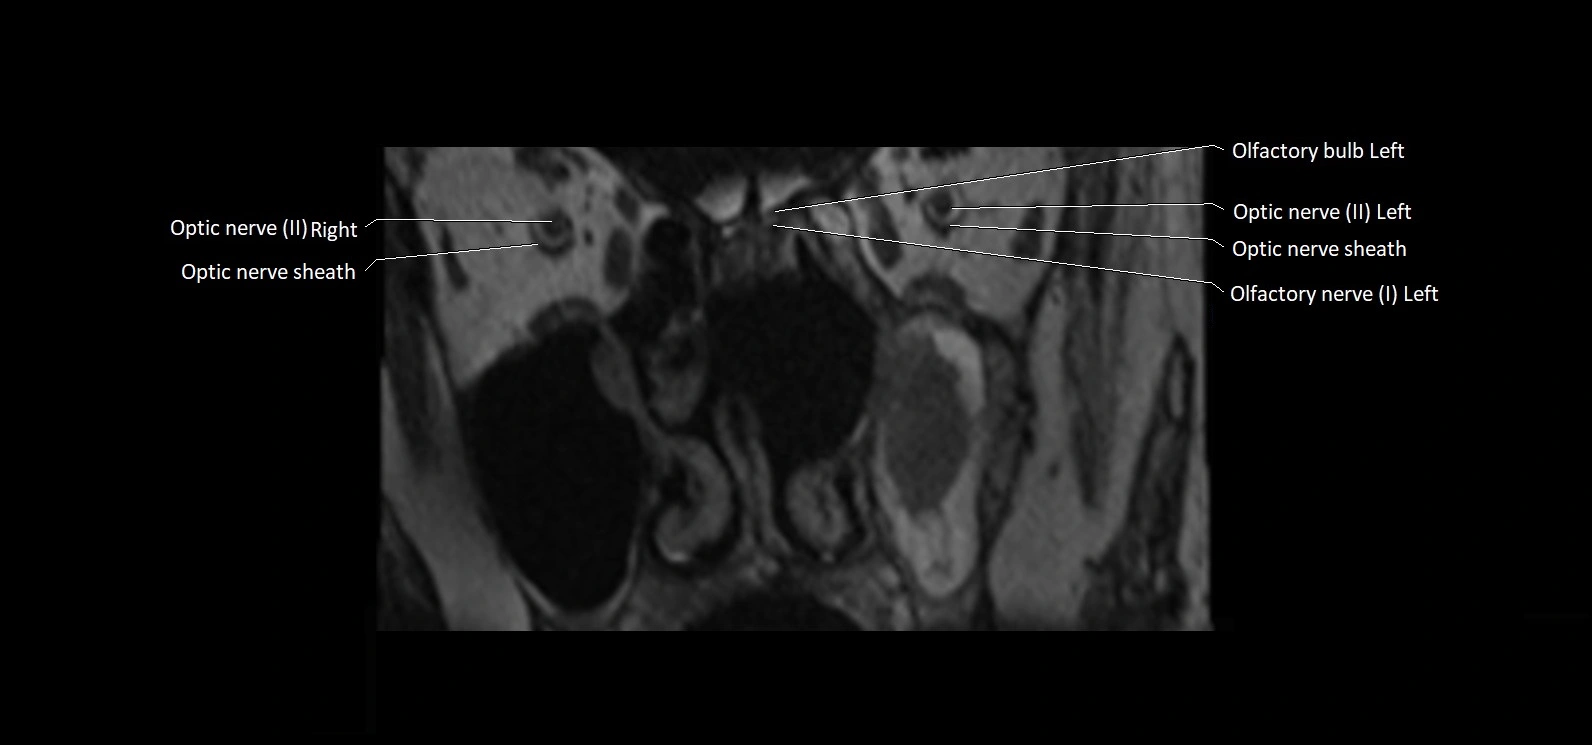

MRI Appearance

• The abducens nerve is a small, thin, linear structure

• Best visualized on high-resolution T2-weighted 3D MRI sequences (e.g., FIESTA or CISS)

• Seen as a hypointense (dark) line running from the brainstem at the pontomedullary junction, traversing the prepontine cistern, and entering Dorello’s canal under the petrosphenoidal ligament, then into the cavernous sinus, and finally the orbit

• May be challenging to visualize in standard MRI due to its small size

• Pathology may be inferred by absence, displacement, or enhancement of the nerve